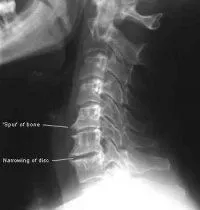

• neck_xray2.jpg Arthritis is caused by the body's response to an increase in load on a joint over a long period of time.

• As the spine is fully matured and is not increasing in size or overall height, it creates instead, jagged outgrowths from the vertebrae are known as spurs, or osteophytes. This eventually causes the spinal soft tissues to become chronically inflamed, and the surrounding bone and joint to degenerate. This is the process known as arthritis.